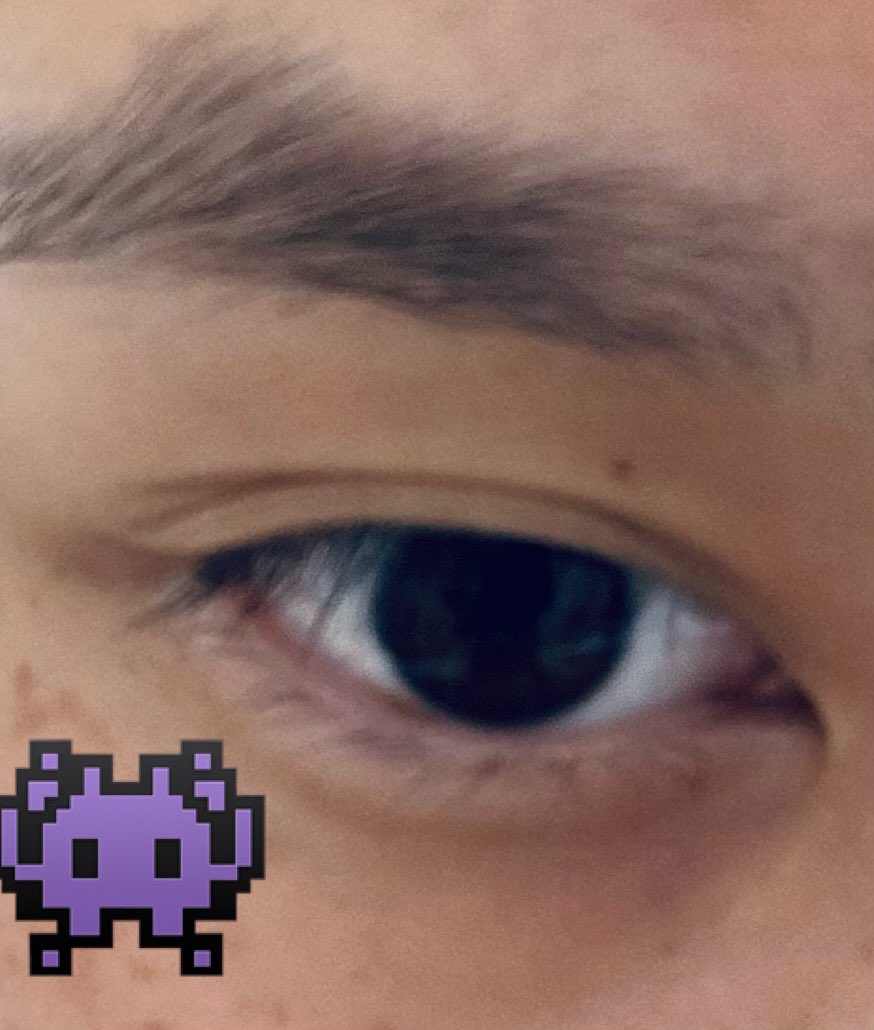

太痛苦了哭一晚上➡️混药物鸡尾酒,经典看不清字但我只会眯一边的眼睛,所以机让我用眼罩()

…为了方便解释于是选了cos的而不是医用的。啊,感觉都是好遥远的事情了。状态栏意识混乱记忆破碎,困到极点下一秒闭上眼就昏迷但是被幻听吓醒——放过我啊

炽烈已极 @AnIncandescence哭出地雷系眼妆x